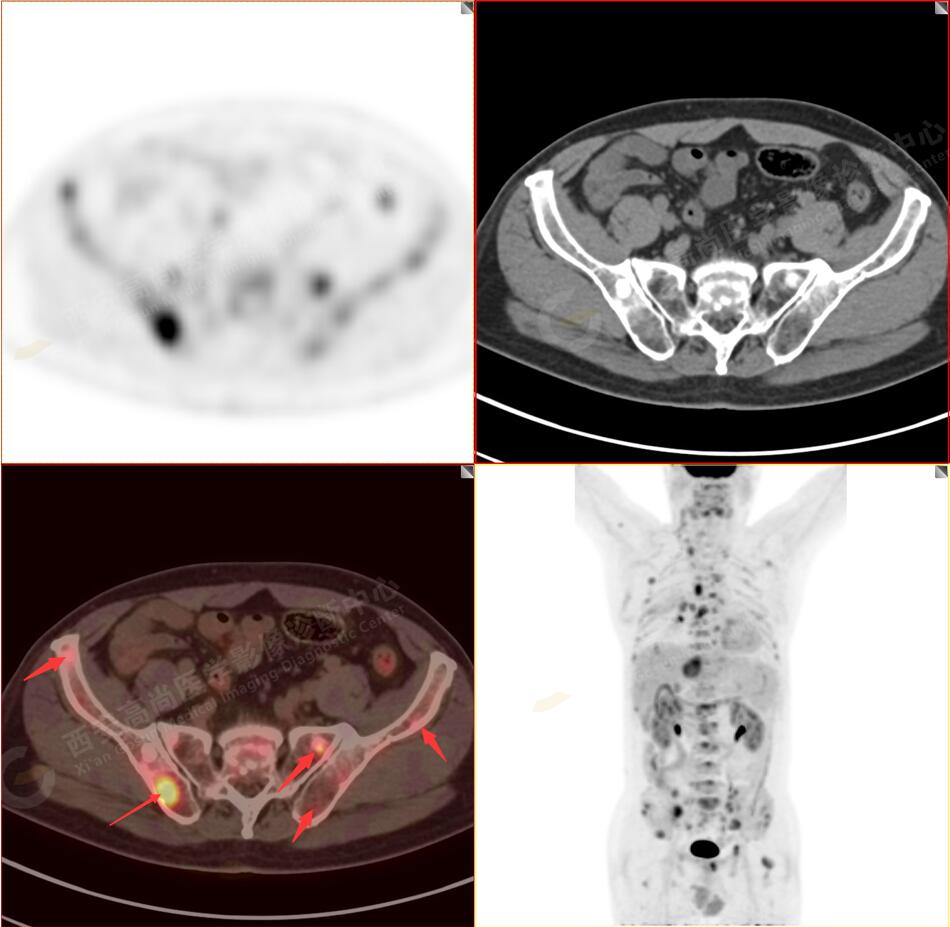

2.以下為全身多發(fā)轉移灶

5.右側肱骨上段、左側肩胛骨、右側鎖骨胸骨端、胸骨、雙側多發(fā)肋骨、脊柱多發(fā)椎體及附件、雙側髂骨、雙側髖臼、雙側恥骨、雙側肱骨上段多發(fā)成骨性病變,呈不同程度FDG代謝異常增高,考慮為多發(fā)骨轉移瘤。